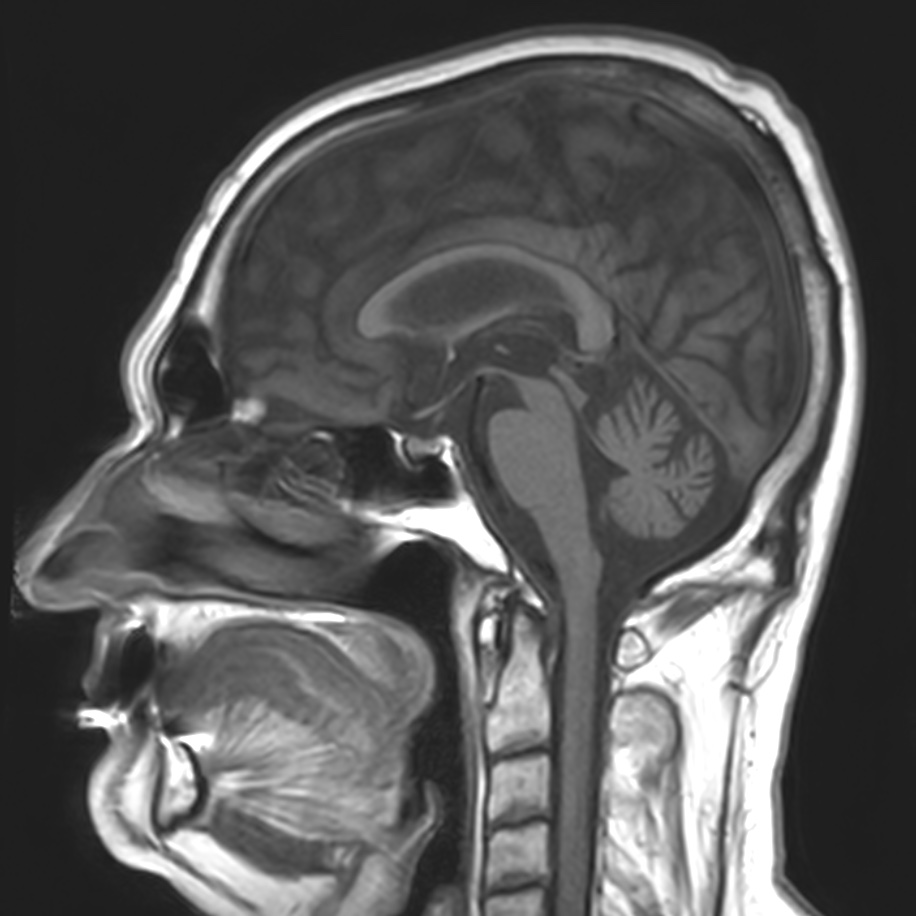

Results: The patient’s BP = 110/70 mm Hg,during the cardiovascular test the arterial pressure did not change.Comprehensive diagnostics of the vestibular analyzer function using computer VNG(videonystagmography)/vHIT at the time of examination-the nystagmus pattern corresponds to vestibulopathy of central genesis-Cerebellar ataxia.Based on the results of an MRI of the brain (3 Tesla),the diagnosis was made:Sporadic adult-onset ataxia; there are signs of isolated cerebellar atrophy in T1 mode

MRI of brain